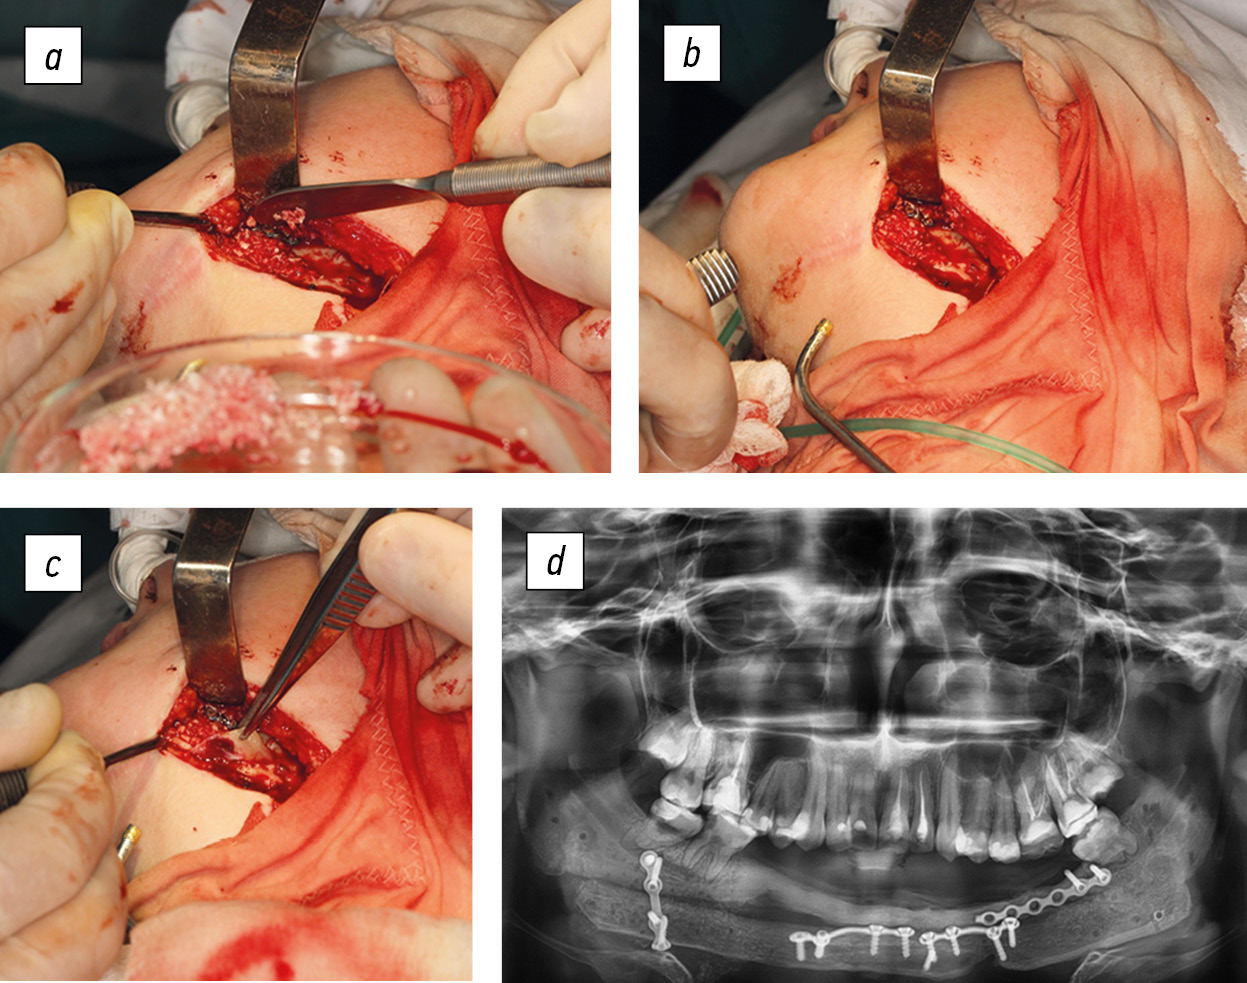

The surgery was performed in the Department of Maxillofacial Surgery of the Turner Scientific and Research Institute for Children’s Orthopedics by two teams of surgeons. One team prepared the receptive bed on the jaw after the removal of the titanium endoprosthesis and then modeled and fixed the bone graft on the jaw. Within 10 years of using a titanium endoprosthesis, under the action of masticatory muscles, a partial remodeling of the stumps of the resected fragments of the jaw occurred, and a bone “bridge” was formed between them. Team 2 of surgeons harvested the vascularized graft from the fibula and made anastomoses on the vessels of the graft and the receptive bed of the jaw. Thus, the surgery consisted of several successive stages, namely, skeletonization of the jaw with an endoprosthesis (the last one was removed), removal through an S-shaped incision in the projection of the fibula of the diaphysis, and addition of feeding vessels, namely, two veins and an artery with a diameter of up to 2.5 mm. Vessels were ligated and dissected, and a fibula fragment of 23 cm long was resected. Then, a transosseous canal was formed through the incision in the ankle area with fixation of the lateral ankle with a bone pin. Thereafter, an osteotomy, fragmentation of the bone graft according to the jaw template, and fixation of its fragments with mini-plates were performed. The integrity of the compact plate and periosteum on one side of the graft and, accordingly, the feeding vessels (arteries and veins) were preserved. The autogenous bone graft was placed along the edges of the fragments and on the surface of the jaw branches and fixed with five mini-plates with screws. Then, vascular anastomoses (9-0 Prolene) were placed between the proximal peroneal artery and the superior thyroid artery and between two more vessels of the donor and recipient zones. The patency test of the anastomoses was positive. Layered sutures were placed on the wound, with passive drainage (Fig. 6).

Fig. 6. Patient B (17 years old). Stages of bone grafting of the lower jaw with a vascularized fibula graft (a–d), and X-ray image of the immediate result of the surgery (e)